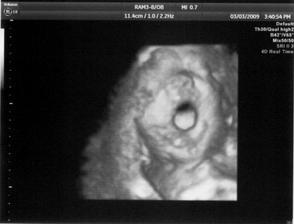

3.3. 4D ultrazvuk, moc hezký zážitek, mimís zíval, máchal rukama a nohama 🙂 a ukázal nám pohlaví 🙂.